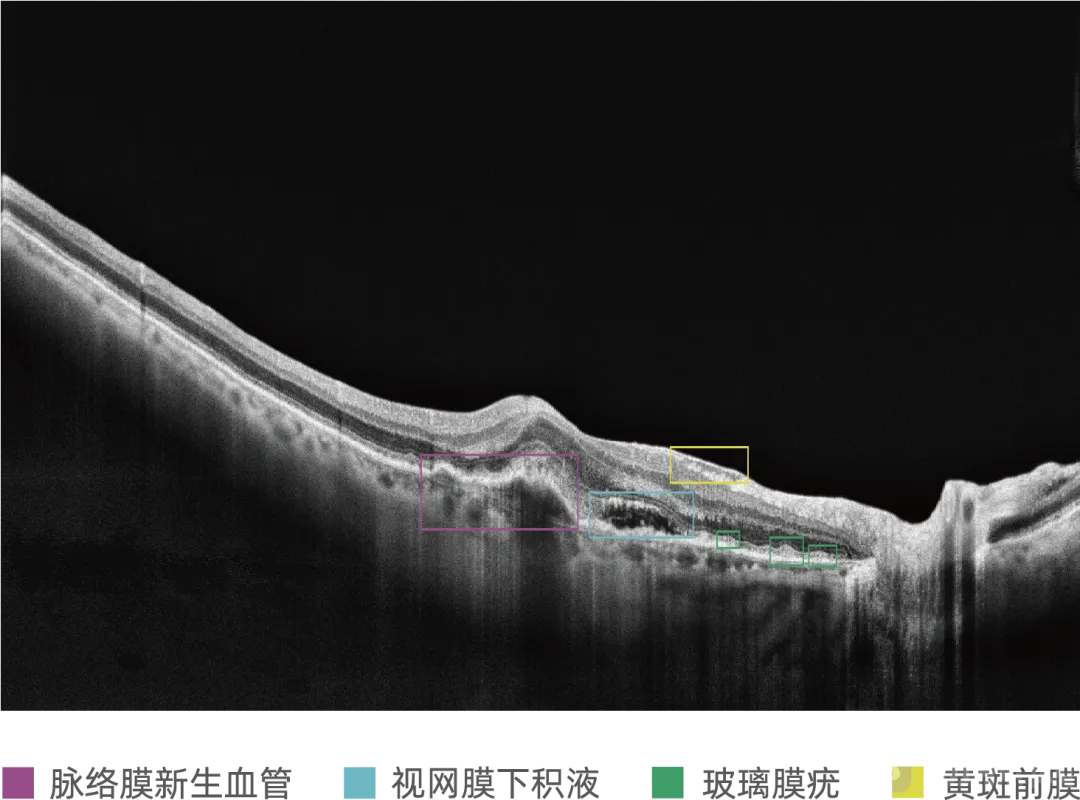

眼科光学相干断层扫描(OCT)影像为眼底三维图像,可清晰呈现视网膜与脉络膜的层次结构及三维形态特征,为精准诊断年龄相关性黄斑变性(AMD)等眼底疾病提供关键形态学依据,是眼科医生重要的临床诊断工具。目前行业获批的眼科AI多基于二维眼底彩照分析;OCT三维体数据较二维图像包含更多空间信息,但也带来了更高的计算复杂度和技术挑战。MIAS-3000通过深度学习算法,自动分析OCT切片图像,精准识别玻璃膜疣、积液、新生血管等病灶信息,为50岁及以上患者提供是否存在中期及中期以上年龄相关性黄斑变性的辅助诊断建议。